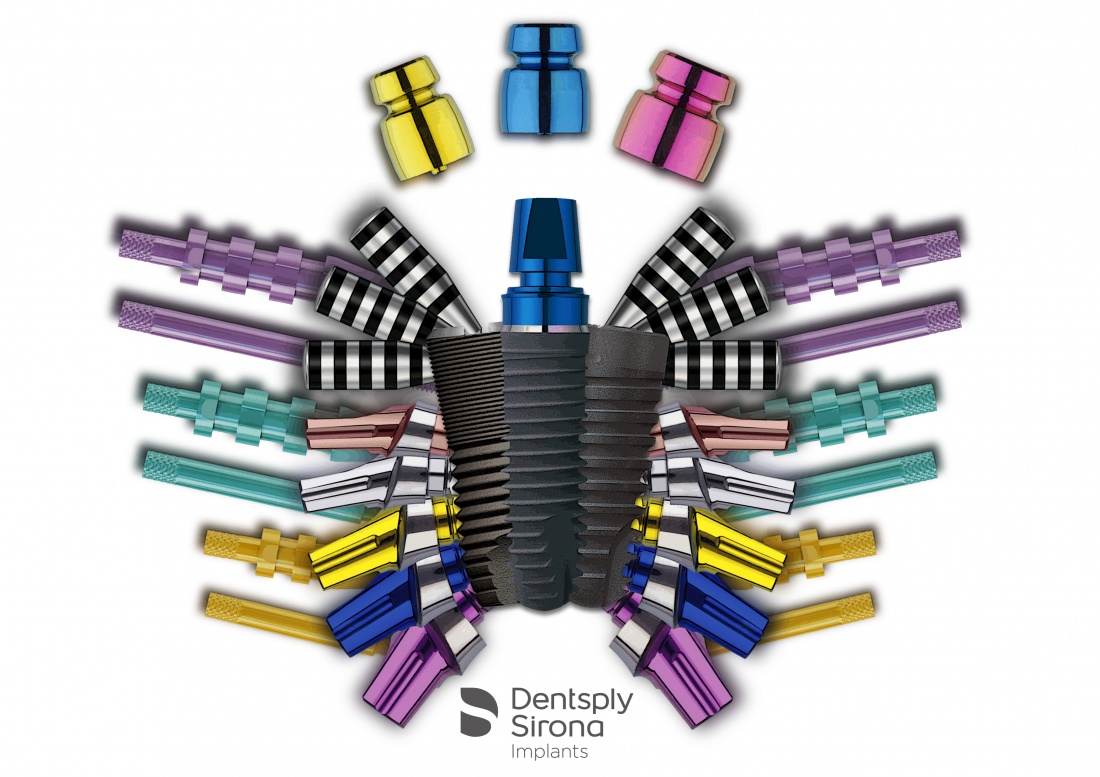

— другие компании, например Dentsply Sirona Implants (изначально Friadent), Dentium и т. д., наоборот, разработали такой дизайн имплантов, который позволяет использовать их в максимально широком диапазоне клинических случаев. Иначе говоря, как первый случай, так и второй, можно решить одним видом имплантов и одним хирургическим протоколом, что, как мне кажется, удобнее и логичнее.

Вот вам еще одно ограничение — количество и варианты супраструктур, которые возможно установить на один имплантат. Чем больше супраструктур (протетических компонентов) — тем выше вариабельность и диапазон клинических случаев, при которых можно использовать данную имплантационную систему.

УНИВЕРСАЛЬНОСТЬ.

Она складывается из двух составляющих:

— макродизайн и размерный ряд имплантов.

— количество и разнообразие супраструктур, которые возможно установить на один имплантат.

Наверное, универсальность — это главное и самое желанное свойство любой имплантационной системы. Выбрав импланты с продуманным макродизайном и максимальным количеством протетических компонентов (супраструктур), вам не потребуется держать в клинике что-то еще, поскольку все клинические случаи вы будете решать в рамках одной системы и одного хирургического протокола, а у ваших ортопедов не будет проблем с подбором протетики.